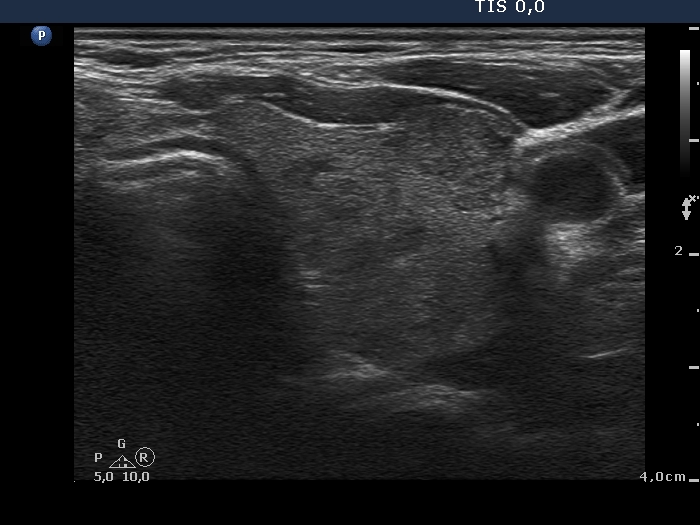

Second examination 6 years later (second row of images):

Clinical data: The patient was referred for a follow-up.

Palpation: unchanged.

Laboratory tests: TSH 3.52 mIU/L.

Ultrasonography. The pattern was the same as in the previous study except for the lesion in the isthmus which has been increased in size.

Suggestion: TSH in a year, ultrasound in 3 years.

Comment. This is the typical presentation of the micronodular form of Hashimoto's thyroiditis.